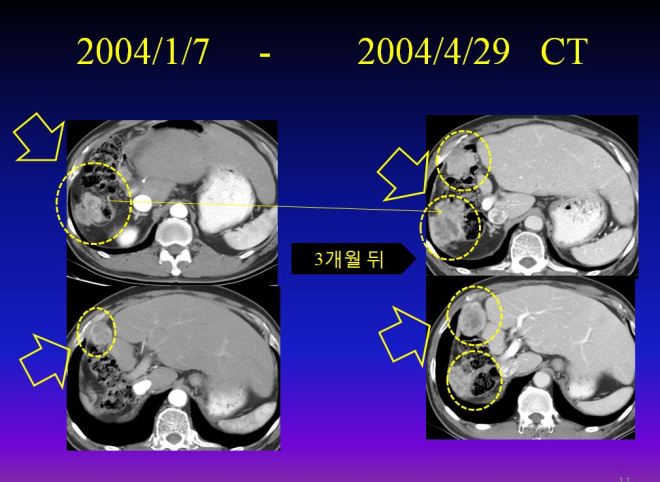

3차 색전술 이후에 이 환자는 매우 종양이 급속도로 자라서 병원에서 이제 한 보름밖에 안 남았다고 판정을 받았다. 다음은 3차 색전술 이후의 사진이다.

위와 같이 초기에 2-3mm 밖에 안 되는 3군데 점으로 보이던 암세포가 색전술 이후에 불과 4개월만에 전간으로 퍼졌다. 그래서 이제 보름밖에 안 남았다는 이야기를 듣고서 내원하게 되었다.

다음은 나의 권유로 식이요법과 라파뮨을 중지하기 전까지 단지 색전술만 하였을 때의 결과이다. 암은 처음에 2월 사진에서 점에 불과 하던 것이 3개월 뒤 주먹만큼 커졌고 또 한달 뒤에 3차 색전술을 하였는데도 불구하고 전체에 퍼졌다.